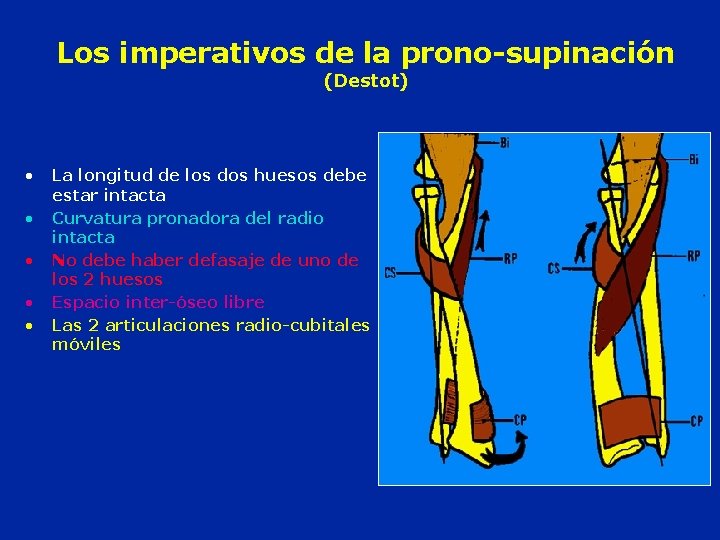

Los imperativos de la prono-supinación (Destot) • • • La longitud de los dos huesos debe estar intacta Curvatura pronadora del radio intacta No debe haber defasaje de uno de los 2 huesos Espacio inter-óseo libre Las 2 articulaciones radio-cubitales móviles